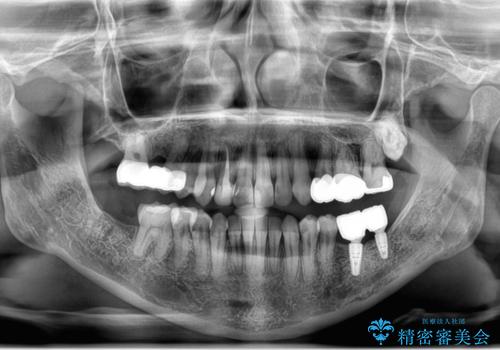

左下の親知らず、左上の小臼歯が残根状態で一本抜いたほかは抜かずに矯正しました。

①保存不可能な歯は抜歯しそのすき間を矯正で閉じる

②右上の親知らずは活かしてブリッジの支台にする

という、予算がかからないように歯を保存する治療計画を立てました。

予算的に右下の一番奥のインプラントは難しかったため、できる限り対応しました。

途中矯正後に妊娠出産、育児等で2年以上中断を経た後虫歯治療の続きを行いました。最終的に治療完了まで行い状態は安定しています。